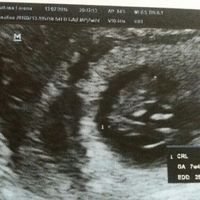

Prima visita fattaaa...

Buong ragazze! Ieri abbiamo fatto la prima visita...da nn crederci ma erano due gemelli omozigoti ma un feto si e'sviluppato nella norma e c era il battito e invece l altro era molto puu piccolo e nn...